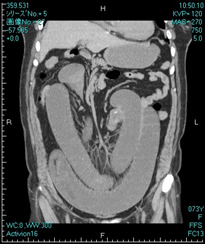

また、従来型のCTが横断面(輪切り)の表示しか出来ないのに対し、16列マルチスライスCT装置では横断面・冠状面・矢上面の3つ以上の断面の表示が可能になりました。このことにより、解剖の全身的な立体関係の位置の確認が容易になり、診断能を高めました。

胸部CT縦隔条件(矢上断面) 体の真横から観察できます。 腹部CT(冠状断面) 体の真正面から観察ができます。

腹部CT(冠状断面) 体の真正面から観察ができます。 肝臓造影CT動脈相 造影剤を使用することでより詳しく診断することができます。